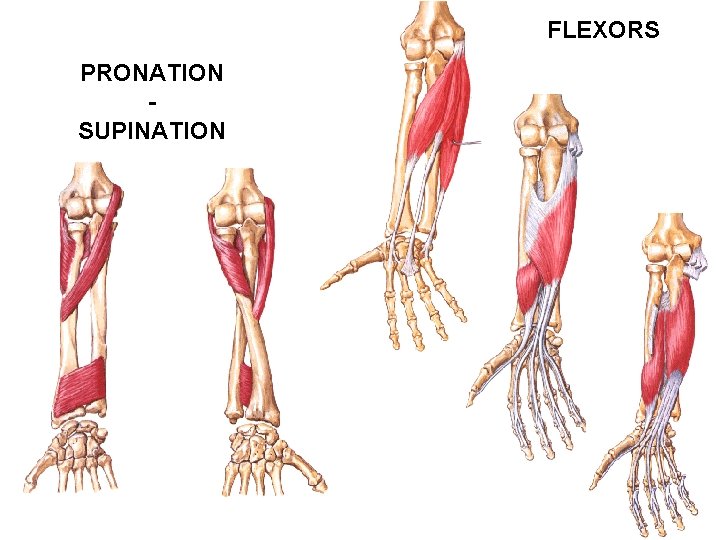

FLEXORS PRONATION SUPINATION